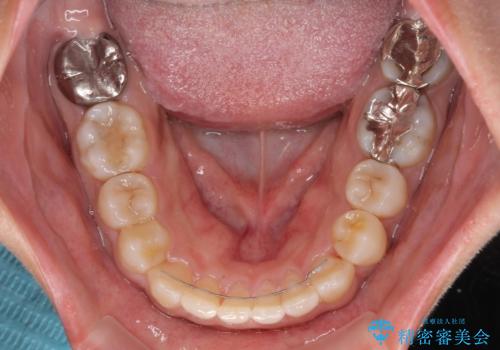

- 上下前歯の叢生を気にして来院された患者様です。

軽度な叢生であり、安価で短期間の治療を規模されていたため、インビザライン・モデレートを用いて矯正治療を行うこととしました。

インビザライン・モデレートは、製作できるアライナーの枚数に制限があるため、移動可能な量に限りがあるものの、インビザライン・ライトよりも枚数が多いため、幅広い症例に対応可能です。